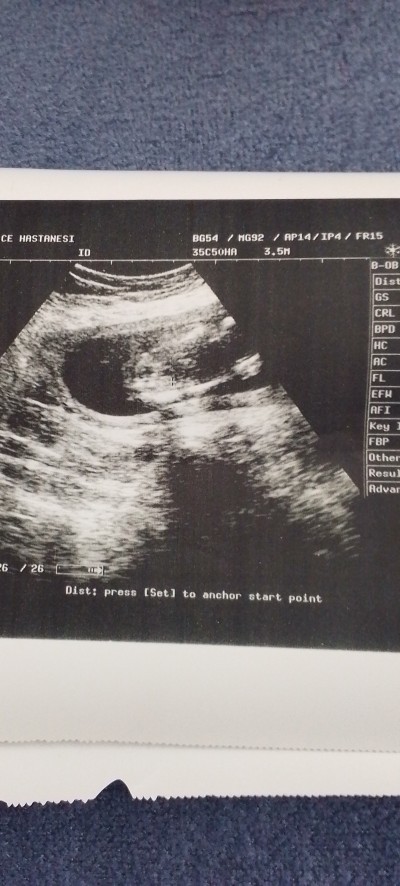

Doktor erkek benziyor dedi ama net bişey demedi iki bacak arası resmi böyle fotoğraf lari olan anneler

Gebelik haftası 18

Canım hiç belli değil ki bacağı kolu bile erkeğe benziyor diyorsa doktor doktoru dinle bidakine kontrole gene git bir baktır bakalım ne dicek

Ama dikkatli bakınca erkeğe benziyor gibide eğer bacağın devamı değilse veya kordonu değilse falan o yüzden belli olmiyo net bulanık ult

Ama dikkatli bakınca erkeğe benziyor gibide eğer bacağın devamı değilse veya kordonu değilse falan o yüzden belli olmiyo net bulanık ultrason